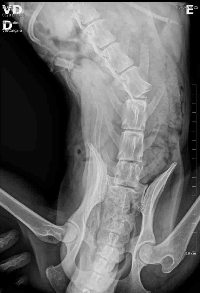

Nosso cachorro foi atropelado (04/03) a coluna foi quebrada, ele precisa de cirurgia urgente até sexta-feira! Pegamos ele da rua, se não for feita a cirurgia será necessário sacrifica-lo e não quero deixar isso acontecer, quem puder divulgar ja seria de grande ajuda